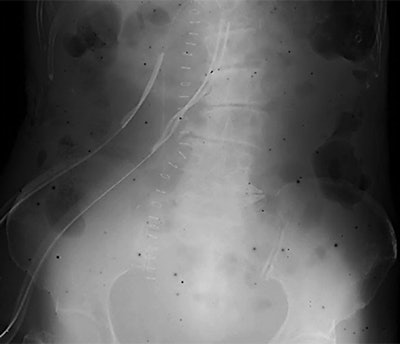

Radiologists at a Japanese hospital were baffled when dark spots began appearing on computed radiography (CR) images in March 2011. They discovered that the spots were caused by fallout from the nuclear disaster at the nearby Fukushima Daiichi nuclear power plant, according to an article in the American Journal of Roentgenology.

Researchers believe the spots represent radioisotopes from the Fukushima Daiichi accident that were suspended in the air as particulate matter. The radioisotopes filtered into CR imaging plates (IPs) to create artifacts on images. Even today, black spots are still appearing on some images, according to the team led by Yasuhiro Kashimura.

The accident spewed radioactive material into the skies and ocean waters around Japan and around the world. As nuclear experts struggled to deal with the disaster, radiology personnel at Iwaki Kyoritsu began noticing black spots on CR images -- a phenomenon also experienced at several other hospitals in Japan.

It didn't take long for staff to connect the black spots to fallout from Fukushima. They tested combinations of imaging plates and cassettes used both before the disaster and after October 2011, when most (but not all) of the fallout had subsided. They found that the spots occurred only in images from old cassettes, which suggests that radioisotopes from the fallout had entered CR cassettes and were adhering to material inside, particularly the cassette's inner lining of felt that acts as a buffer for the imaging plate.

Kashimura and co-author Koichi Chida, PhD, confirmed their suspicions using optical microscopy, which detected pieces of suspended particulate matter in the felt of an older cassette in use at the time of the disaster. They cut out the piece of felt and inserted it into a new cassette in which the latent image had been erased from the imaging plate. Black spots appeared, corresponding to the locations on the piece of older felt.